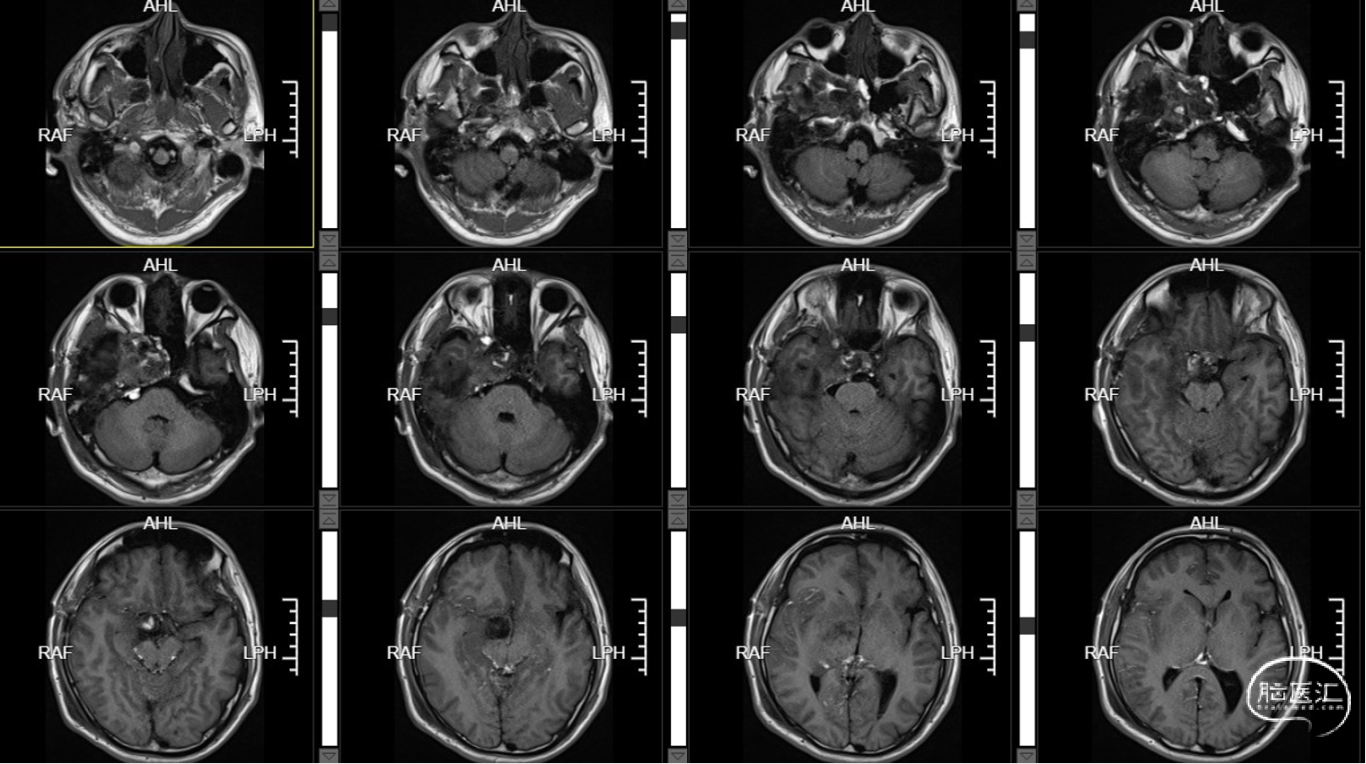

术前T1+C